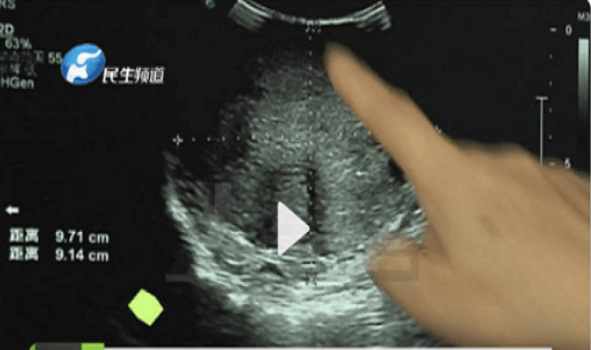

Mời độc giả xem thêm video: 70% bệnh nhân ung thư gan được phát hiện muộn (Nguồn video: THĐT)